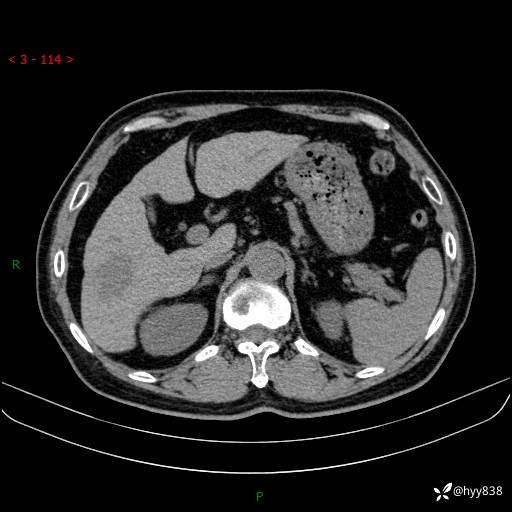

增强动脉期